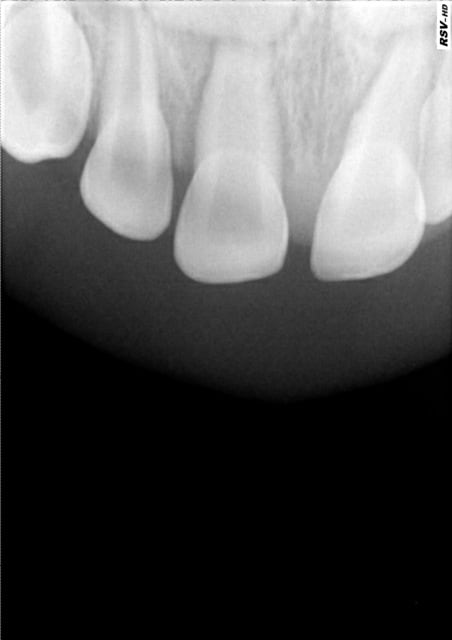

Patiente de 30 ans qui consulte pour bilan. 21 est dyschromique (brune) et ne répond absolument pas au test au froid. La lumière canalaire est rétrécie dans les 2/3 apicaux. La dent est asymptomatique. ATCD de choc il y a 8 ans.

Pas de symptômes, lumière canalaire rétrécie en direction apicale (en comparaison avec l'autre centrale), dans un premier temps je ne ferais pas de traitement endo et tenterais un blanchiment externe ou une facette en cas d'échec du premier traitement. Si la patiente est sous surveillance régulière, rien n'empêche d'être plus invasif ensuite, et dans le cas présent pas d'urgence.